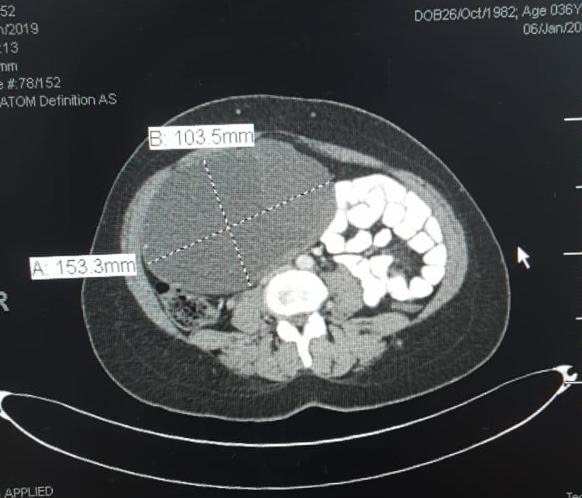

Laparoscopic approach for huge benign ovarian cyst in woman with history of previous 5 laparotomies (including 4 cesarean section)

An adnexal mass (mass of the ovary, fallopian tube, or surrounding connective tissues) is a common gynecologic problem. In the United States, it is estimated that there is a 5 to 10% lifetime risk for women undergoing surgery for a suspected ovarian neoplasm. Adnexal masses may be found in females of all ages, from fetuses to older adults, and there are a wide variety of types of masses. Today, the surgical treatment has become more conservative and less invasive; hence, a laparoscopic approach in the presence of benign cysts has become a golden standard. In the past, patients with previous abdominal surgery were discouraged from undergoing laparoscopic surgery because of its increased risk of bowel injury caused by needle and trocar insertion. Complications occur two times more frequently in patients with previous laparotomy in a study of long series. The potential risk for injury of organs adherent to the abdominal wall during veress needle or trocar insertion as well as the necessity for adhesiolysis and its attendant complications are the two major specific problems constraining surgeons from performing laparoscopic cystectomy/ oophorectomy for patients with previous abdominal surgery. Herein, we report a case of a 32-year-old woman P4 + 2 with history of previous four cesarean section and a following laparotomy for interval sterilization presented to our clinic with abdominal mass, discovered by ultrasound scan, managed by a laparoscopic approach.